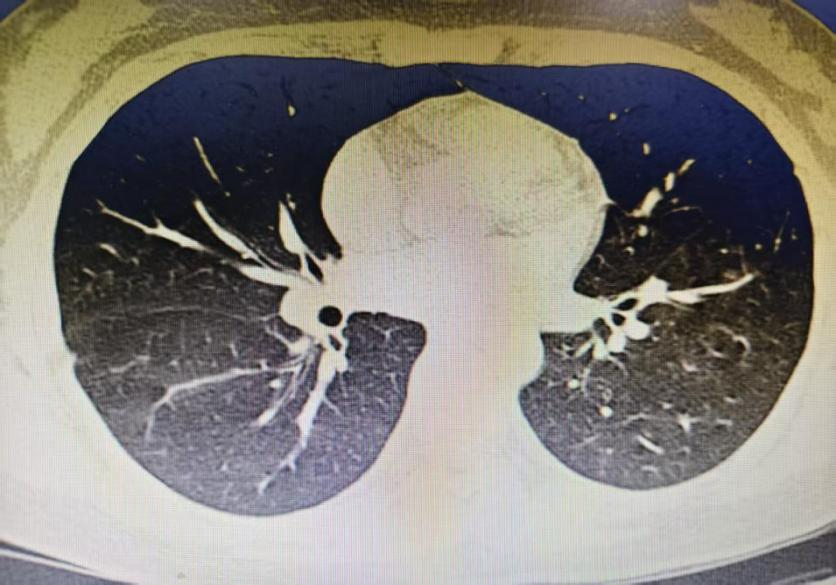

抵达石大一附院急诊医学中心时,院内抢救团队早已严阵以待。持续心肺复苏、呼吸机辅助通气……监护仪的每一次波动都牵动着所有人的心。终于,在多学科医护人员的共同努力下,患者恢复了自主心率。随后,以“呼吸心跳骤停、呼吸衰竭、吸入性肺炎”等诊断转入EICU,接受进一步救治。 入院时,患者仍处于深昏迷状态。头颅CT提示脑水肿,胸部CT显示双肺背段实变、支气管闭塞——误吸导致的严重气道阻塞和肺部感染,成为救治过程中必须闯过的关键难关。 随后,EICU团队迅速联系呼吸与危重症科刘冬主任医师,急诊行电子支气管镜检查。镜下可见隆突及各叶段支气管黏膜充血明显,右肺中下叶及左肺下叶被粘稠痰液堵塞,常规吸引难以清除。在机械通气、抗感染、脑保护及器官功能支持的基础上,医疗团队对双肺多个肺段实施支气管镜灌洗治疗。随着粘稠痰液被逐步清除,气道恢复通畅,为呼吸功能改善创造了重要条件。 经过一周的全力救治,患者意识逐渐清醒,自主心率与呼吸平稳恢复,生命体征趋于稳定。复查胸部CT显示,双肺渗出性病变较入院时明显吸收,气道通畅,各项指标显著好转。4天后,患者顺利脱机并拔除气管插管,转出内科EICU。 此次成功救治,是石大一附院“以患者为中心”理念的生动实践。从院前急救的果断处置,到院内生命支持的精准施策,再到后期治疗的细致入微,每一个环节都凝聚着急诊医学中心团队的专业与担当。医护人员时刻关注患者的点滴变化,及时调整治疗与护理方案,用医学的严谨和人性的温度,陪伴患者走过最艰难的时刻。正如一位参与救治的医生所说:“我们不只是抢救一个生命,更是守护一个家庭的希望。” 生命在医患同心的呵护下重新绽放。石大一附院急诊医学中心将继续秉持“救死扶伤、大爱无疆”的职业精神,不断提升急危重症救治能力,为守护边疆各族人民的生命健康筑牢坚实防线。 供稿|急诊医学中心 张天 秦练 编辑|朱思佳 编审|于 磊 王晓民 权江宏 杨 涛